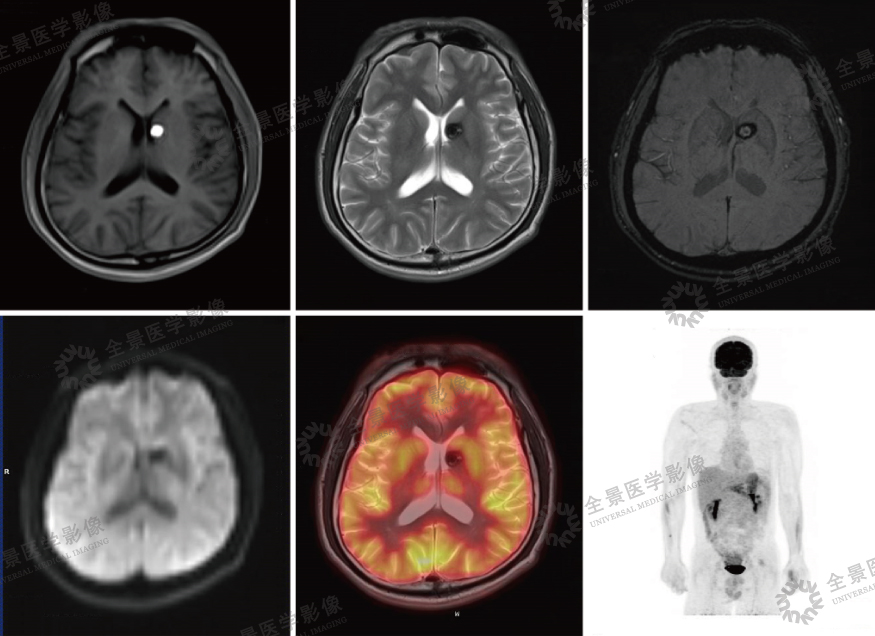

案例:中年男性,PET/MR发现脑内左侧基底节区一直径约1.2cm的结节,PET/MR通过多序列扫描,协助诊断。

结论:本例运用了SWI(磁敏感加权成像)清晰显示了海绵状血管瘤伴出血的特征。